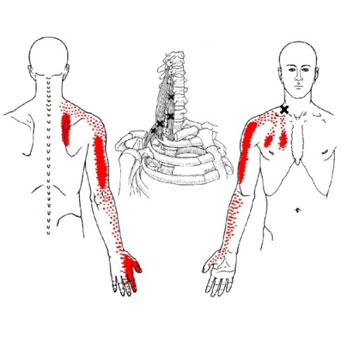

Oui! La douleur peut être causée par le syndrome myofascial et les points trigger myofasciaux. Ce n’est pas une maladie imaginaire, le syndrome myofascial et les points myofasciaux existent vraiment et malheureusement ils sont peu connus de notre système de santé traditionnel. Ils peuvent vous rendre la vie misérable. Eh, oui! Les points trigger ont passé l'art de mimer les symptômes de certaines maladies, de quoi laisser perplexe le meilleur des médecins.

Pour moi qui suis massothérapeute, ils font partie de mon quotidien. Je traite des gens à tous les jours avec des douleurs aux épaules, au cou, aux genoux, mal de dos, etc. Il m’arrive souvent de voir des gens qui ont très mal et qui ne savent plus quoi faire pour soulager leurs maux. Malheureusement, la massothérapie est souvent leur dernier recours. Ils ont souvent tout essayé, mais leurs douleurs persistent. Dans bien des cas il s’agit d’un durcissement du fascia et de points trigger. De deux à trois traitements suffirent dans bien des cas pour qu’ils retrouvent leurs qualités de vie qu’ils avaient auparavant.

Ils me disent tous la même chose! J’aurais dû venir te voir avant, car j’ai dépensé une fortune en médicament et en traitement! Alors la prochaine fois que vous avez une douleur quelconque, il se pourrait bien que la cause soit le syndrome myofascial et les points trigger myofasciaux!